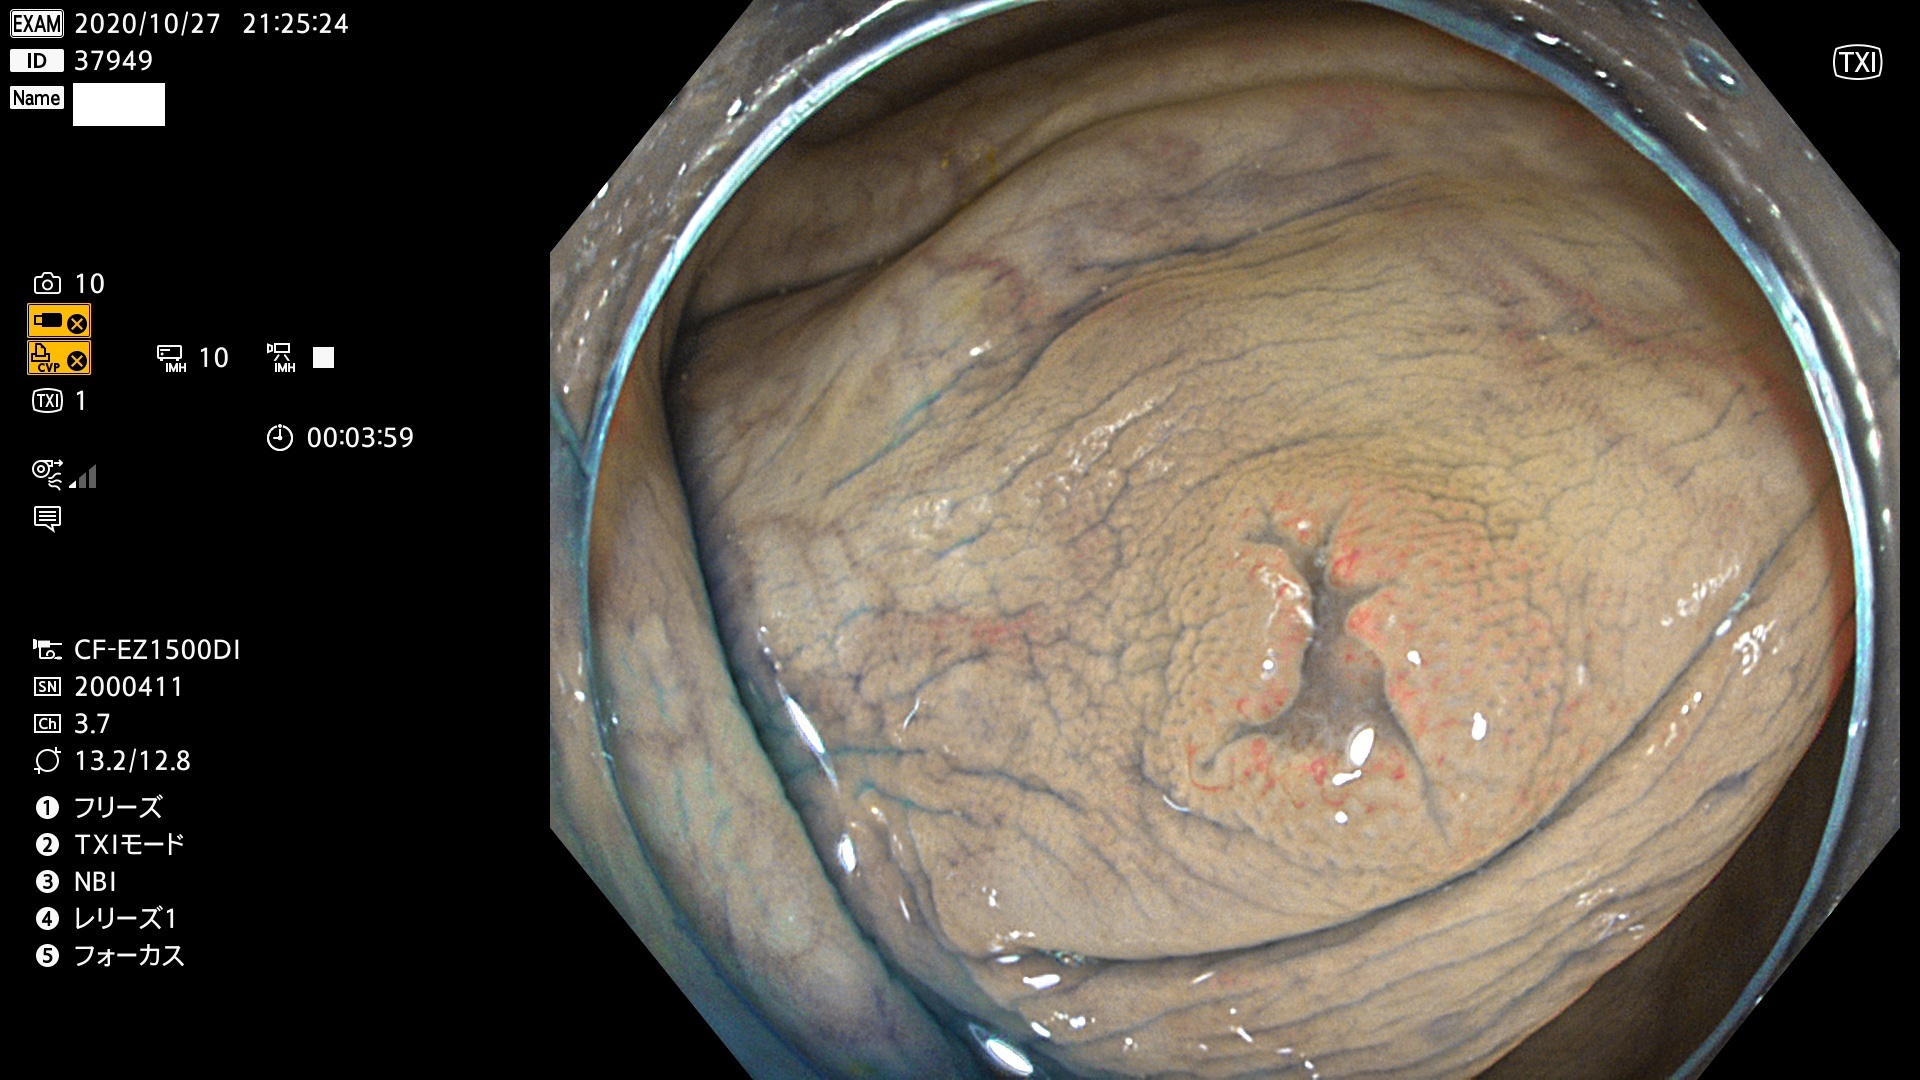

発見困難で危険性の高い平坦型病変(上記100名より抽出)

37900 37902 37903 37904 37905 37906 37907 37909 37910 37911 37912 37913 37914 37915 37916 37917 37919 37921 37922 37923 37926 37928 37929 37930 37931 37933 37934 37935 37936 37937 37938(SSAPのみ) 37939 37940 37941 37942 37943 37946 37947 37948 37949 37951 37952 37953(SSAPのみ) 37955 37956 37957(SSAPのみ) 37958(SSAPのみ) 37960 37962 37963 37964 37966 37967 37968 37971 37972 37973 37975 37976 37977 37979 37982 37983 37984 37985 37986 37987 37988 37989 37990 37991 37992 37993 37994 37995 37996 37998 37999